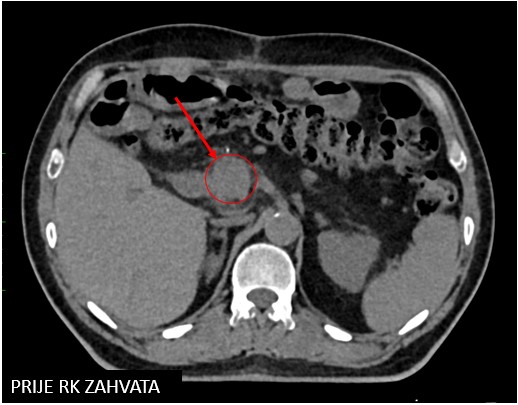

gušterača 59 3agušterača 59 3b

Rezultat – 45 mjeseci nakon RK

Potpuni nestanak tretirane lezije